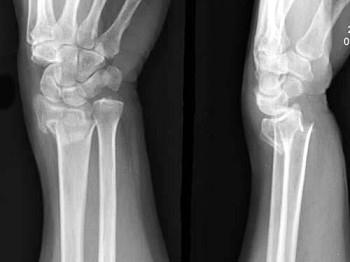

有外伤史,结合图像,最可能诊断是?(?)A.Smith骨折B.尺骨骨折C.未见异常D.Colles骨折E.腕关节脱位

问题 有外伤史,结合图像,最可能诊断是?(?)

选项 A.Smith骨折 B.尺骨骨折 C.未见异常 D.Colles骨折 E.腕关节脱位

答案 D